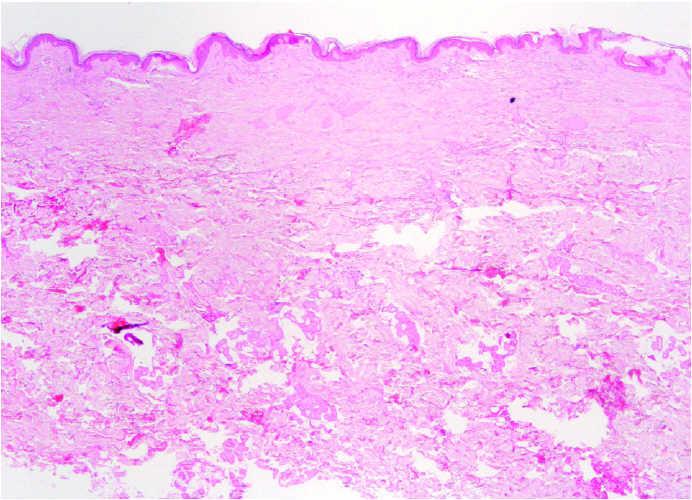

Fig. 3.--Biopsia de placa en espalda. Marcada fibrosis en dermis papilar y reticular superficial. (Hematoxilina-eosina, ×20.)

En la biopsia de la placa de la espalda (fig. 3) se observa un fragmento de piel con discreta hiperqueratosis y de forma más significativa, una marcada fibrosis en forma de haces colágenos gruesos dispuestos de forma compacta en la dermis papilar y reticular más superficial; asimismo se observan ligeros infiltrados perivasculares de células redondas. No hay alteraciones en dermis profunda ni en el tejido celular subcutáneo.